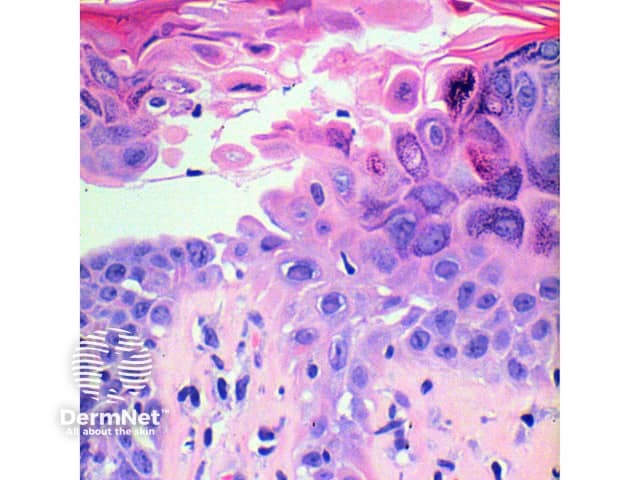

The scanning power view of the histology of Darier disease is of an epidermal and superficial dermal inflammatory process (Figure 1). Intraepidermal separation may be visible at this power, which on closer inspection is seen as suprabasal acantholysis (Figures 2 and 3). Acantholysis can be seen at all levels within the epidermis. Dyskeratosis of the keratinocytes is seen, with two notable changes described. Corps ronds refer to cells with small pyknotic nuclei, a perinuclear clear halo and eosinophilic cytoplasm (Figures 4 and 5).

Grains are compressed cells with elongated nuclei seen in the stratum corneum and granular layer (Figures 4 and 5).

The overlying epidermis exhibits compact orthokeratosis, which can form a prominent focal plug.

Figure 4

Figure 5